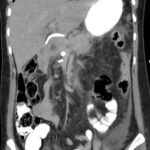

Tomografía de abdomen y pelvis con cte ev: del 13/10/2023.

Complicaciones posquirúrgicas

Tomografía de abdomen con cte ev: del 20/10/2023.